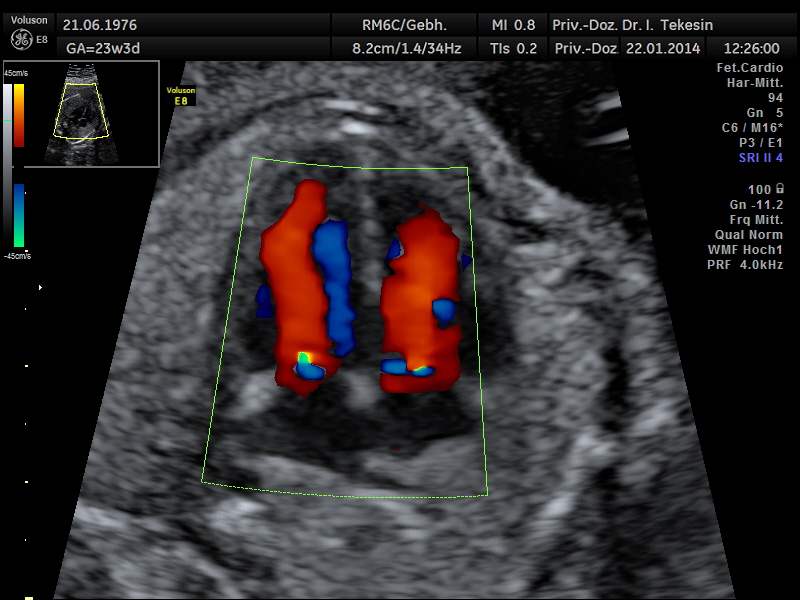

Fetale Echokardiographie

Ein weiterer Bestandteil der weiterführenden Ultraschall-Diagnostik ist die Beurteilung des kindlichen Herzens und der großen Blutgefäße, die fetale Echokardiographie. Dabei untersuchen wir die Lage, Größe und Symmetrie des Herzens, Anatomie der Herzstrukturen, Funktion der Herzklappen, Herzfrequenz und die Lage der großen Gefäße. Mit Hilfe der farbkodierten Doppler-Sonographie des Herzens werden weitere Details untersucht: die Funktion der Herzkammern, Herzscheidewände, Blutflüsse im Herzen und Blutflüsse in den großen Gefäßen.

Das Ziel dieser Ultraschalluntersuchung des fetalen Herzens ist der weitest mögliche Ausschluss von angeborenen Herzfehlern. Die Voraussetzung hierfür sind eine spezielle Ausbildung und Erfahrung des Arztes in Verbindung mit der hohen Qualität des Ultraschallgerätes.

Dopplersonographie

Auch das Durchblutungsverhalten in der Nabelschur und in den Gebärmuttergefäßen wird mit Hilfe des Doppler-Ultraschalls dargestellt. Diese Untersuchung ist eine ergänzende Untersuchung im Rahmen der US-Feindiagnostik und ermöglicht eine Beurteilung des Blutflusses in den kindlichen und mütterlichen Gefäßen mittels einer speziellen Technik. Bei dieser Untersuchung wird die Blutströmung farbig und akustisch dargestellt. Die Geräusche, die man während der Untersuchung hören kann, entstehen durch technische Effekte (Doppler-Effekt), welche der Untersucher und die werdende Eltern hören können, jedoch nicht das ungeborene Kind.

Durch Darstellung der Blutflussmuster in den mütterlichen Gefäßen (Arterie uterina rechts und links) zwischen der 20.-25. SSW können Feten mit dem Risiko einer späteren Mangelversorgung (Plazentainsuffizienz) entdeckt und somit im weiteren Schwangerschaftsverlauf optimal überwacht werden. Ein erhöhtes Risiko für die Entwicklung einer Präeklampsie (mütterlicher Bluthochdruck und Eiweißausscheidung im Urin) kann ebenso festgestellt werden.

Die Beurteilung des Blutflusses in den kindlichen Gefäßen (Nabelschnurarterie [A. umbilicalis], A. cerebri media und Ductus venosus) ermöglicht eine Aussage zur Versorgung des ungeborenen Kindes. Die Doppleruntersuchung kann in unterschiedlichen Zeitpunkten der Schwangerschaft durchgeführt werden.

Normaler Vierkammer–Blick mit Farbe

Normaler Vierkammer-Blick mit Farbe